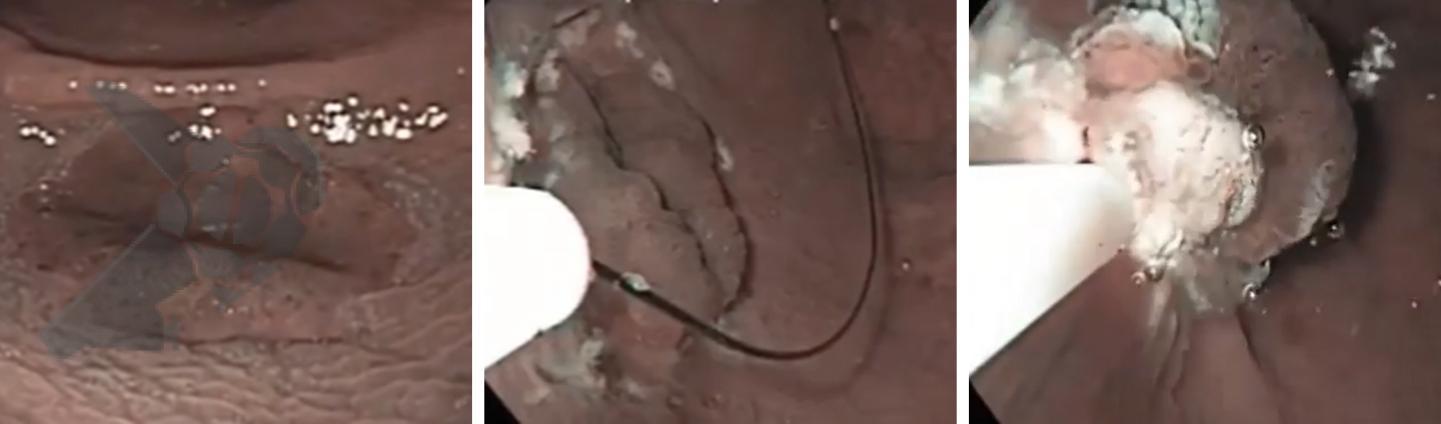

Pólipos superficiais (“flat”) são desafiadores porque costumam estar presos por fibrose submucosa, que impede a elevação com a injeção. A UEMR resolve isso: a flutuabilidade transforma a lesão plana em uma lesão polipoide, permitindo profundidades significativamente maiores (1.238,7 μm vs. 731,6 μm; P<0,01).

Debaixo d’água, a força de flutuação supera a fibrose e libera a base da lesão, facilitando a captura pela alça.

Figura 2. Mucosectomia underwater. Lesão plana de reto. Infusão de água seguida de captura da lesão com alça, sem injeção.